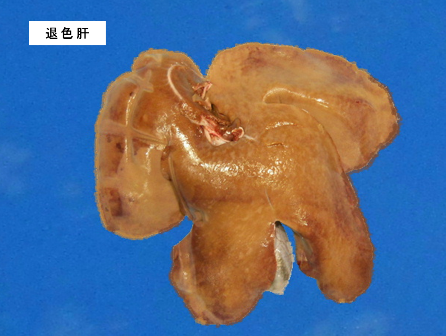

退色肝

肝臓が脂肪変性をおこし、多くの中性脂肪が蓄積して通常よりも淡い色で見える状態を退色肝といい、肝臓は廃棄となります。

脂肪変性は、過食や過肥、カビ毒や薬物中毒などによっておこります。

写真左は退色肝、右は正常の肝臓です。